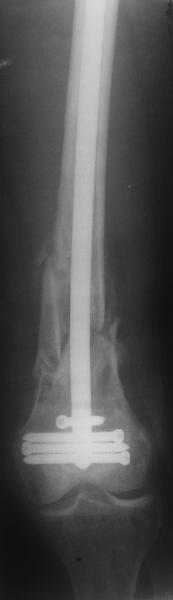

По прямой проекции неплохо. Что за стержень?

Антеградный остеосинтез при дистальных переломах бедра мы применяем давно, этот материал обобщен в канд. диссертации Александра Виноградского.

Предприятие ЦИТО выпускает доработанные нами гвозди, которые хорошо годятся для дистальных переломов, да и недороги. Можно вводть в дистальное овальное отверстие 3 винта, которые заклинивают друг друга.

Большеберцовые стержни отлично выполняют роль ретроградных бедренных. Конечно, которые не 9, а 12 мм в диаметре.

Примеры приложены.